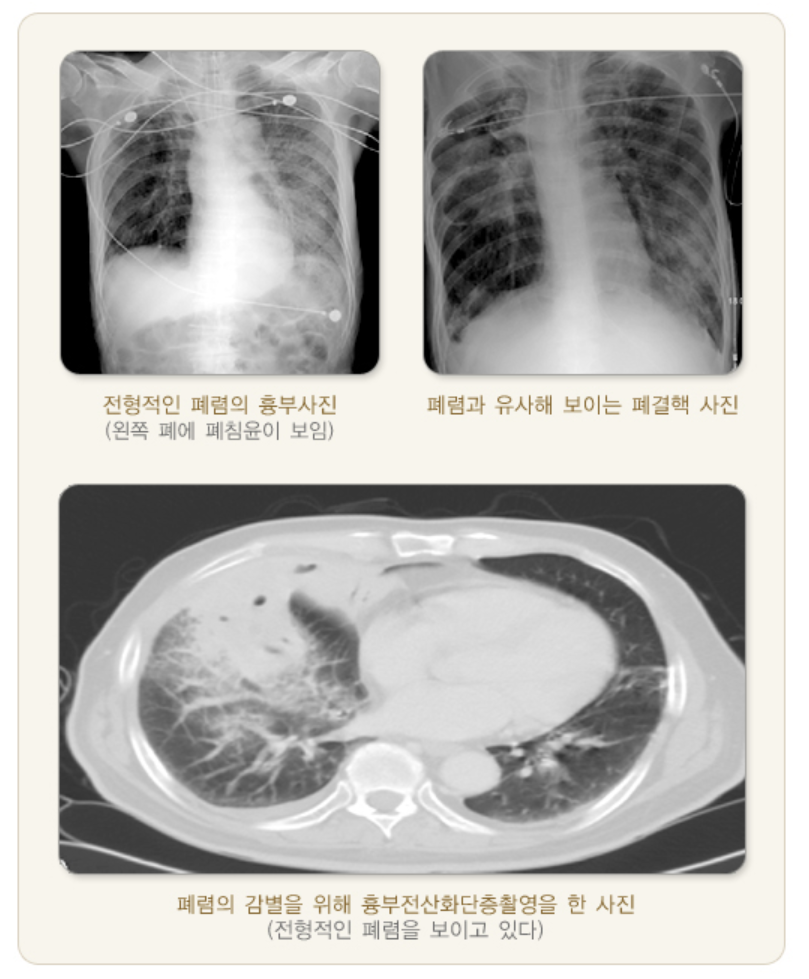

1. 가슴 X선 촬영

임상 증상과 진찰만으로도 진단이 가능하지만, 대부분 가슴 X선 촬영이 필요합니다.